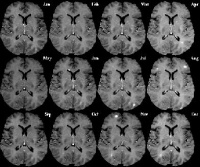

脑部及脊髓核磁共振:最好有显影剂显示新的病灶。在脊髓炎病患、完成脊髓核磁共振後、是否需加做脑部核磁共振的意见仍然莫衷一是。不过、若是定位在脑部的发作、即使是第一次发作、50-65%病患部核磁共振已经有不正常。通常T2-weighted影像是基本的检查、施打显影剂後显示新的T1-weighted病灶表示有急性发作。